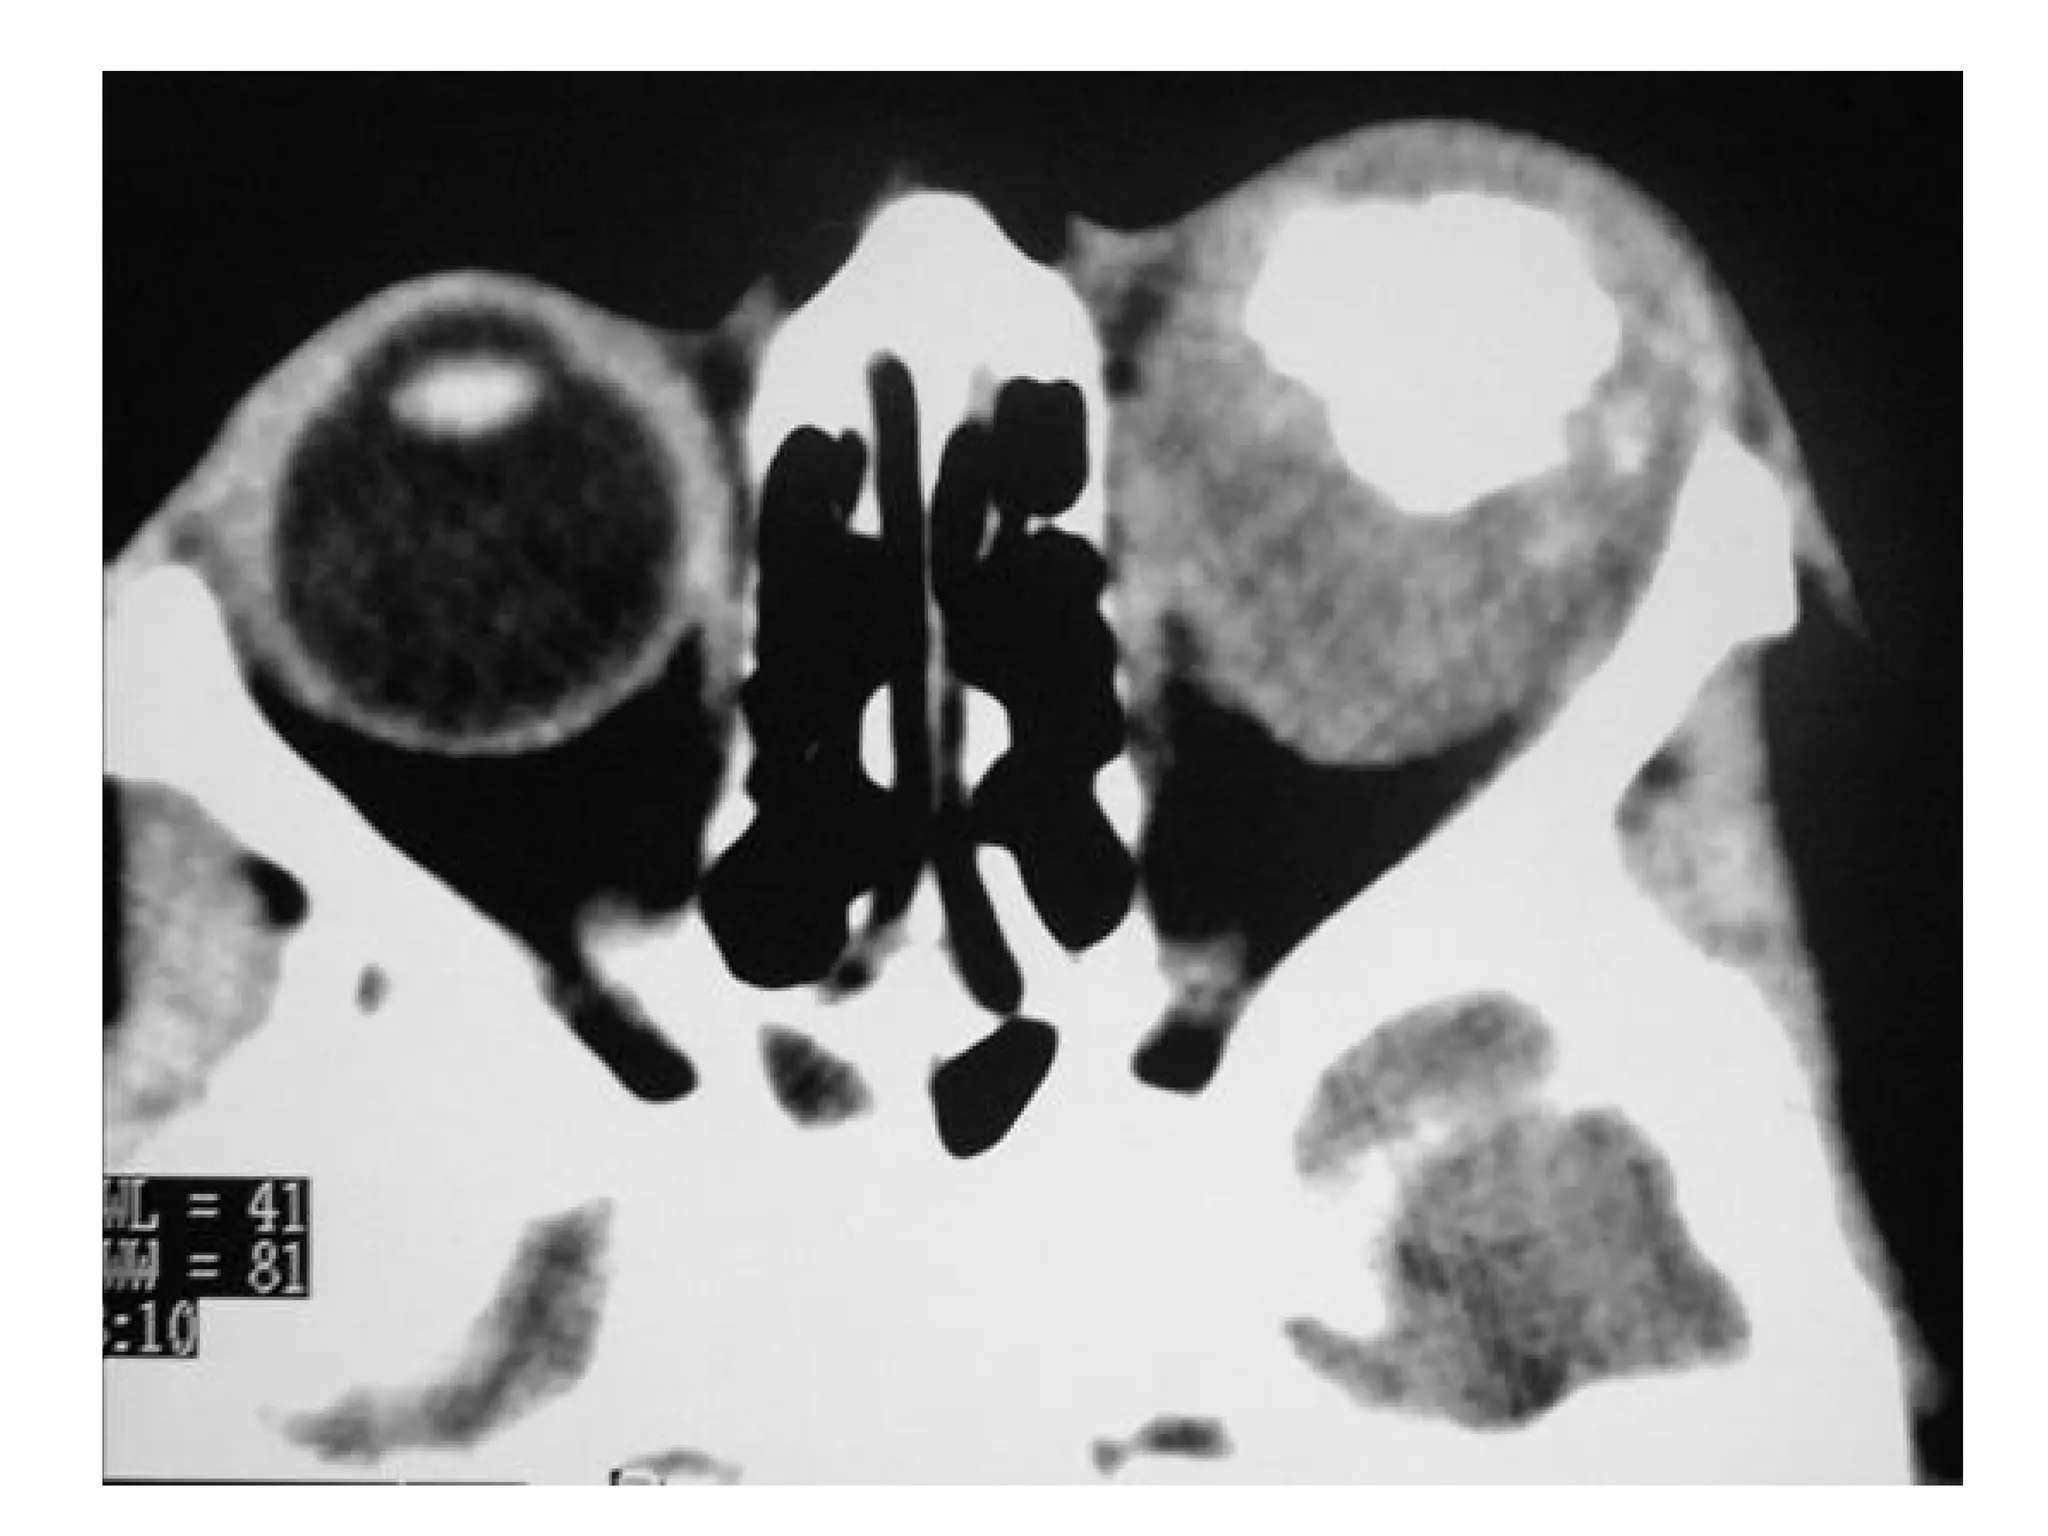

c) Radiographic Features :

1-CT :

-The optic nerve is variably enlarged and the mass may

either be fusiform or exophytic in appearance ,

additionally the nerve may be elongated with kinking

or buckling

-Enlargement of optical canal ; >1 mm difference

between left and right is abnormal

-Lower CT density than meningioma

-Contrast enhancement variable

-Calcifications rare (but common in meningioma)